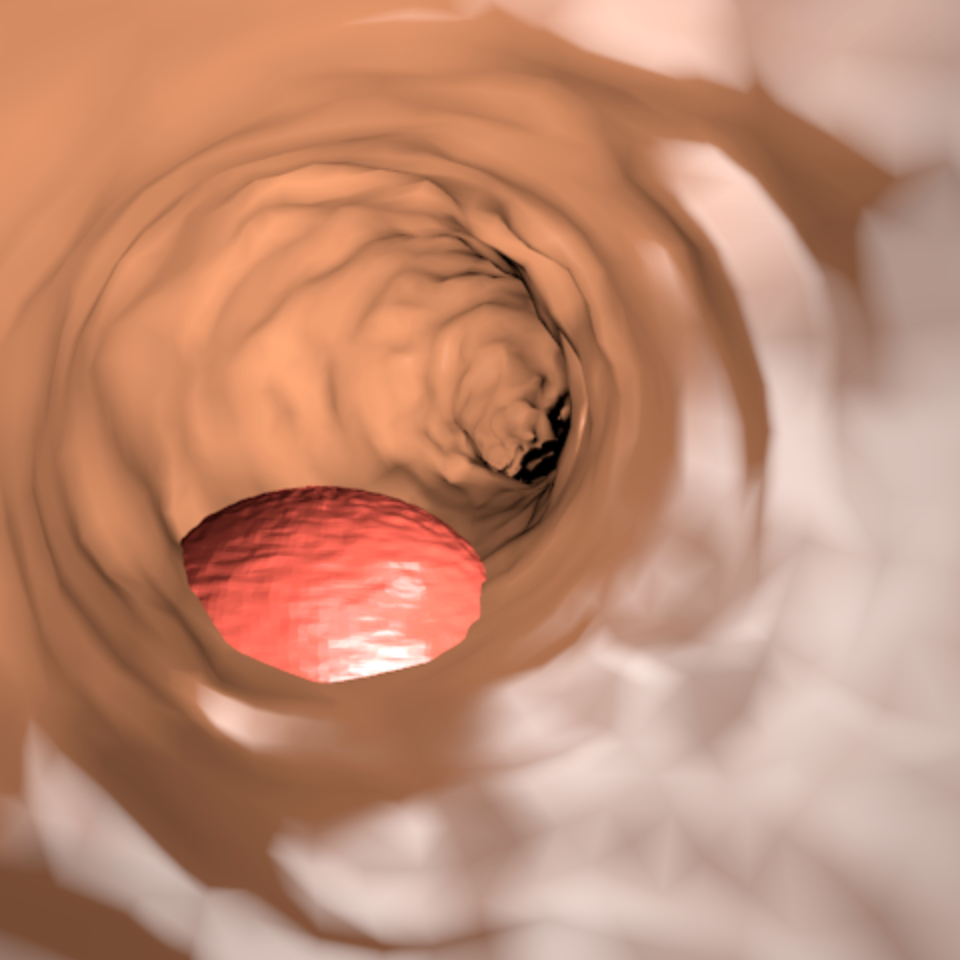

We release Synth-Colon (see Figure 1), the largest synthetic dataset for polyp segmentation including additional data such as depth and 3D mesh.

4 Synth-Colon

We publicly release Synth-Colon, a synthetic dataset for polyp segmentation. It is the first dataset generated using zero annotations from medical professionals. The dataset is composed of 20 000 images with a resolution of 500500. Synth-Colon additionally includes realistic colon images generated with our CycleGAN and the Kvasir training set images. Synth-Colon can also be used for the colon depth estimation task [12] because we provide depth and 3D information for each image. Figure 1 shows some examples from the dataset. In summary, Synth-Colon includes:

Synthetic images of the colon and one polyp.

Masks indicating the location of the polyp.

Realistic images of the colon and polyps. Generated using CycleGAN and the Kvasir dataset.

Depth images of the colon and polyp.

3D meshes of the colon and polyp in OBJ format.